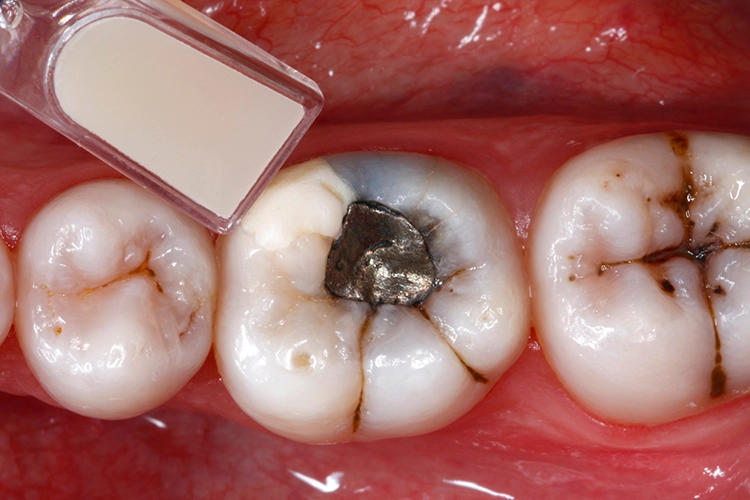

Anschließend wurden sämtliche Kavitätenränder mit einem Feinkorndiamanten nachgearbeitet und finiert. Danach wurden die pulpanahen Kavitätenareale mit einem selbstlimitierenden Polymer-Rosenbohrer (Polybur, Gebr. Brasseler GmbH & Co. KG, Lemgo) substanzschonend exkaviert (Abb. 7), eine Exposition der Pulpa konnte mit diesem Vorgehen der selektiven Exkavation vermieden werden (Abb. 8) [51–55]. Das pulpanahe Dentin im Zentrum der Kavität wurde mit einer dünnen Schicht röntgenopaker Calciumhydroxidpaste auf wässriger Basis (Calcicur, VOCO) indirekt überkappt (Abb. 9). Das Calciumhydroxidpräparat wurde mit einer partiellen Unterfüllung aus lichthärtendem kunststoffmodifiziertem Glasionomerzement (Ionoseal, VOCO) abgedeckt (Abb. 10).